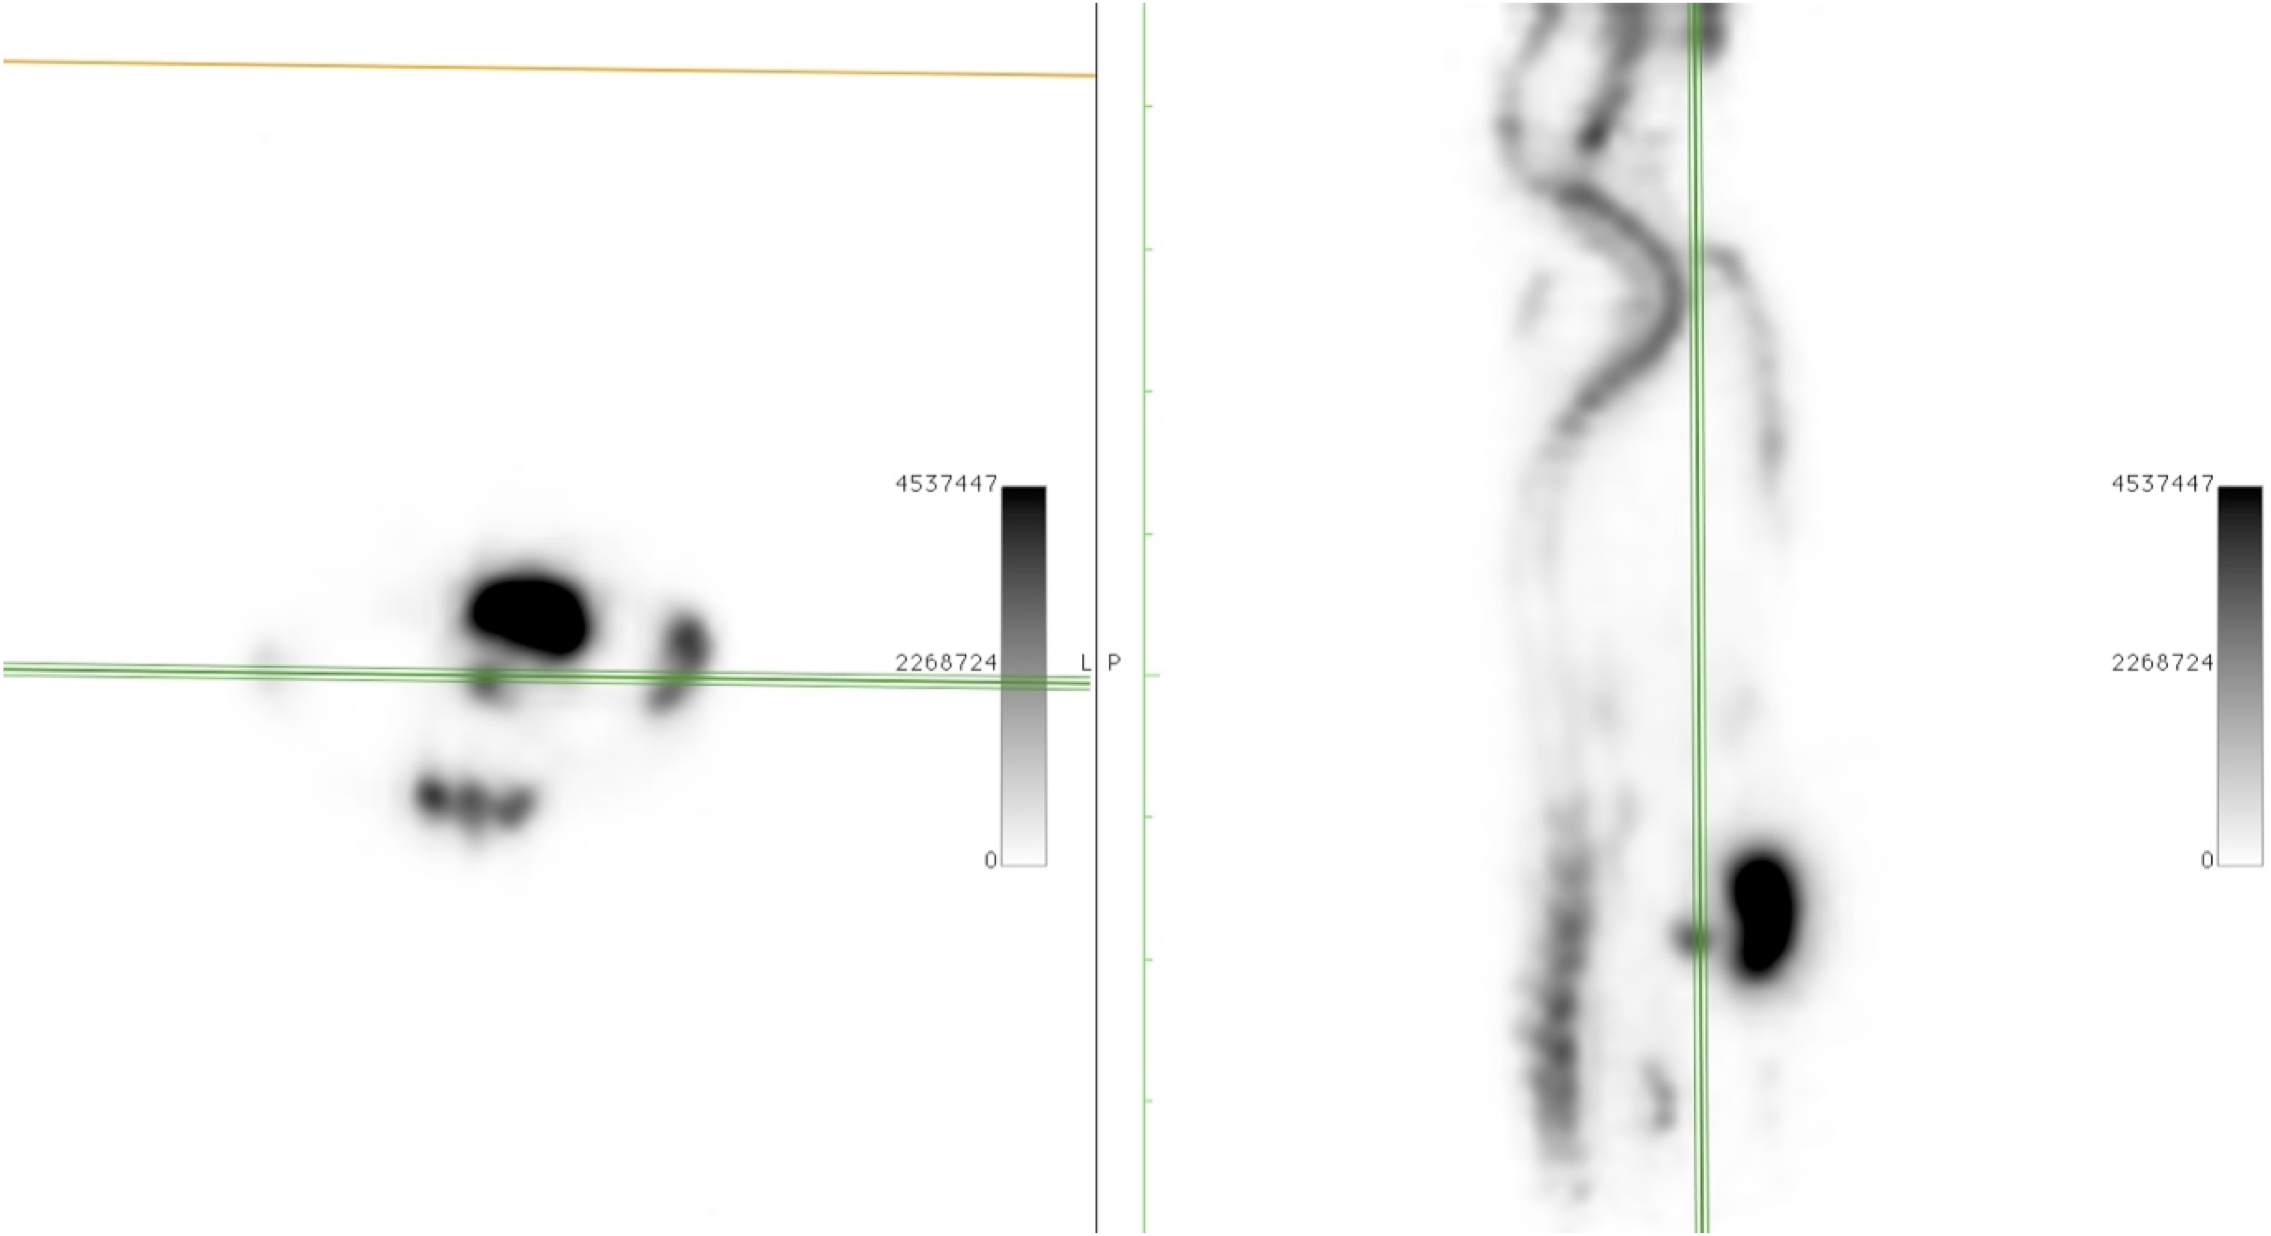

CASE 2: Mouse PET dynamic imaging for tracer development

Research objective: Dynamic PET image (MIP-coronal view) of a mouse injected with an experimental 18F-labelled tracer showing the function of renal and hepatobiliary system and subsequent uptake in the gallbladder.

Animal model: Mouse, 20-25g

Acquisition protocol: Acquisition time: 90 min Number of bed position: 1

Processing and reconstruction protocol: 18 x 5 min frame, 250 - 750 keV 3D OSEM, 0.855 mm isotropic voxel size

Biomarker or contrast agent: Experimental 18F-labelled tracer;Injected activity: 6 MBq;Intravenously via tail vein